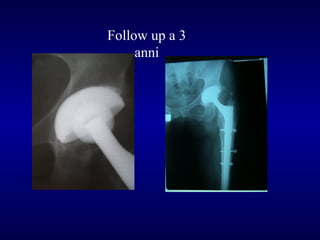

Paprosky 1

Post-op

F.U. 6 anni